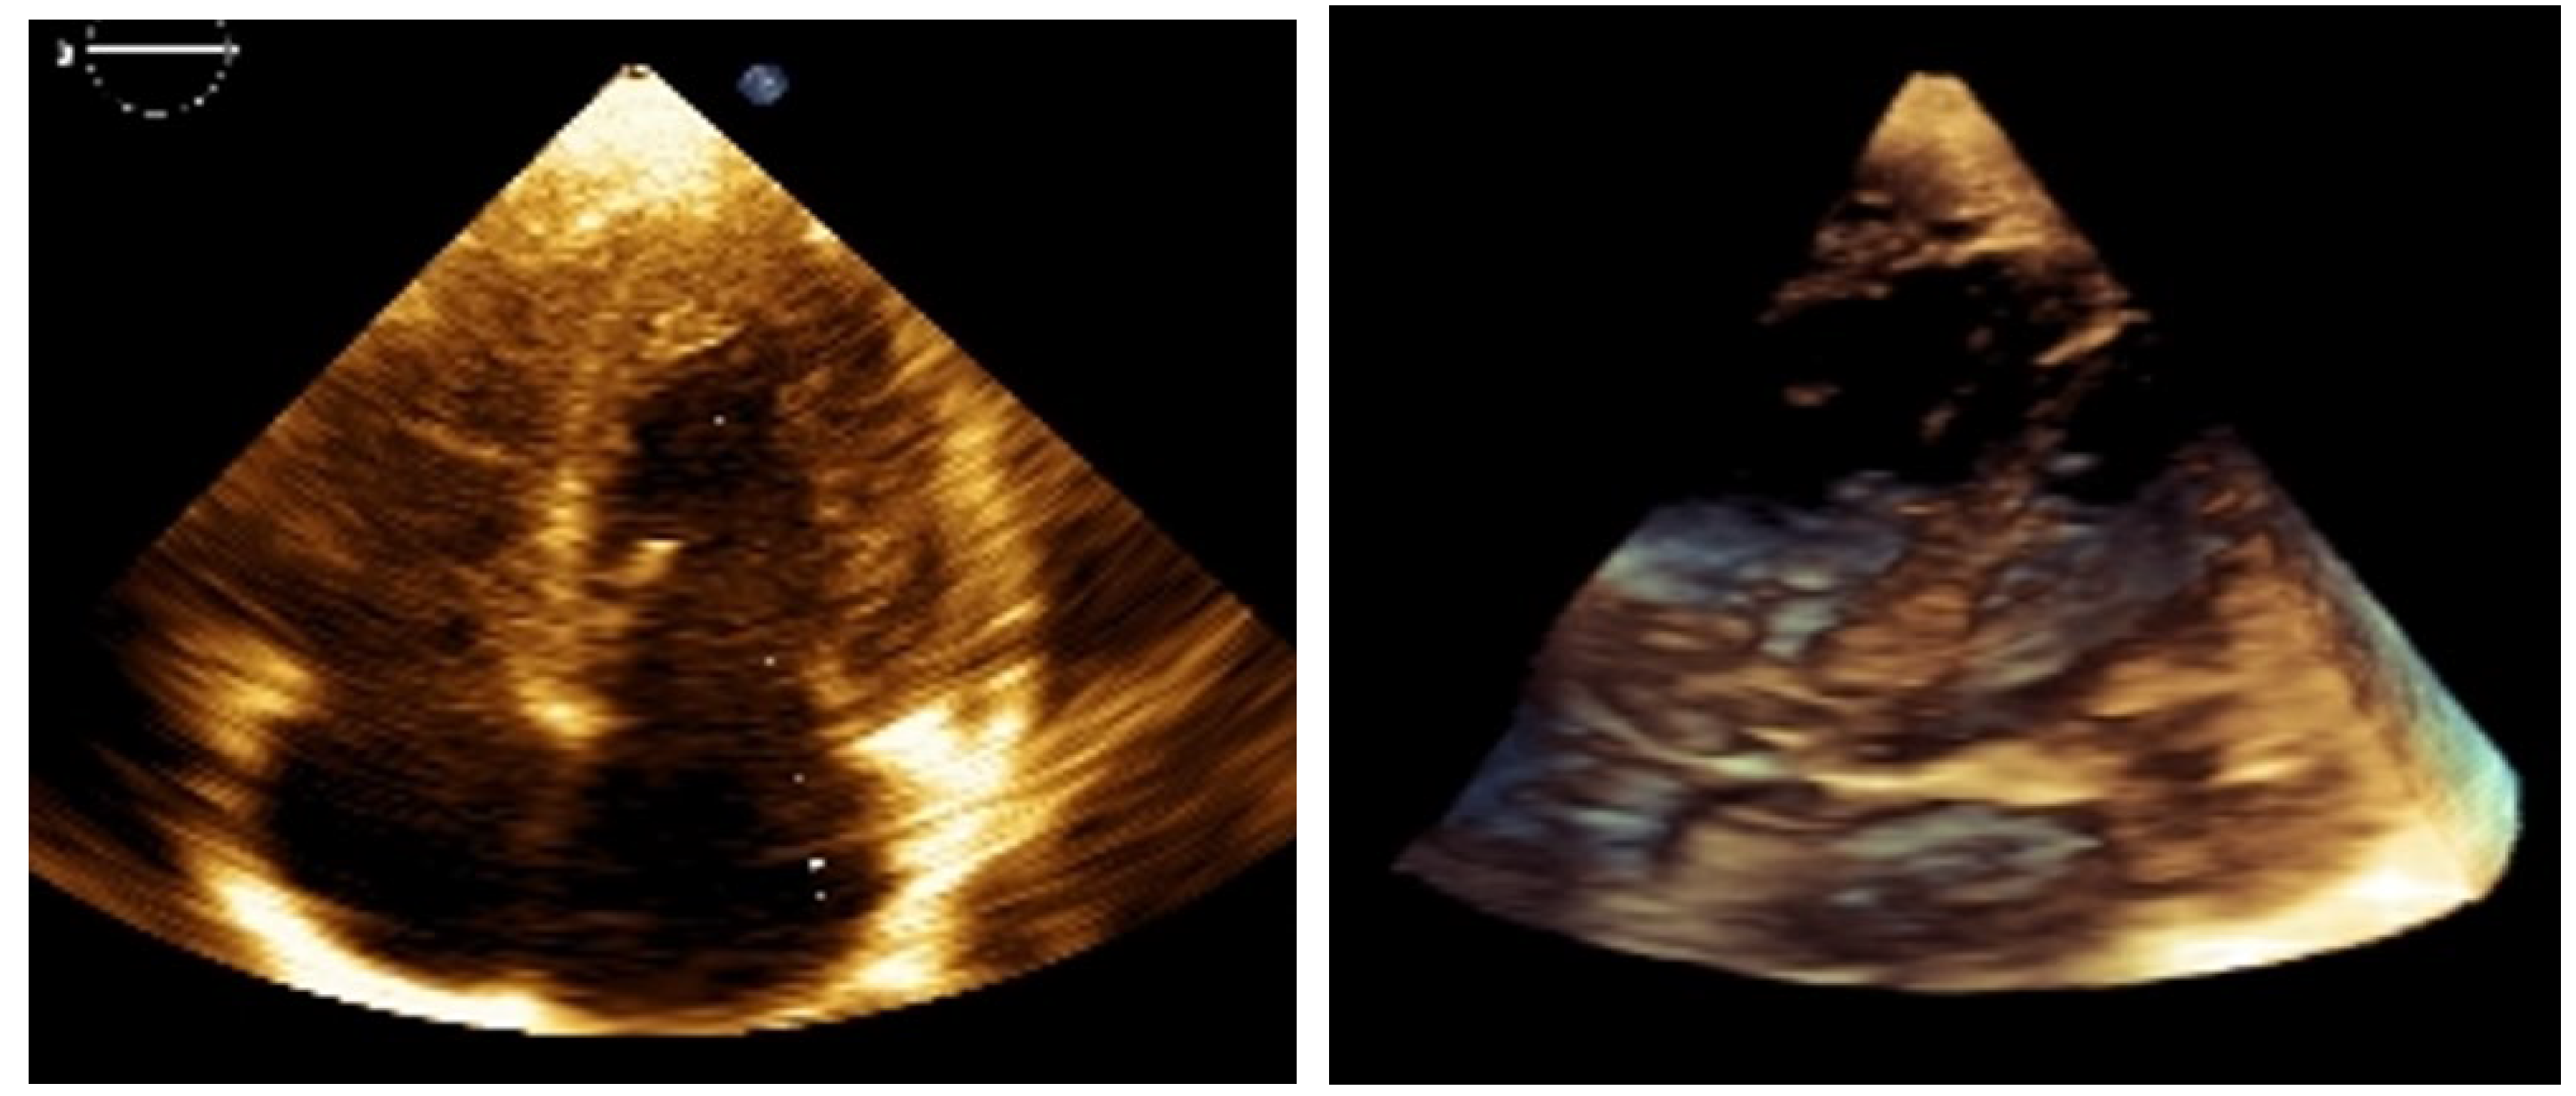

Figure 2.

2D and 3D images at 9 months post-treatment. Everolimus therapy (Rapamune) began at 3 months of age. Sirolimus, administered as an oral suspension, was started at a weight-adjusted dose based on the standard 1 mg/m² once daily (1 m² ≈ 30 kg). Serum levels were monitored every 8 weeks (therapeutic range: 4–10 ng/mL), and dose adjustments were made accordingly. Toxicity was assessed using CTCAE v3.0. SEGA response was evaluated using RECIST v1.1. Follow-ups were conducted at 6 and 9 months via echocardiography and at 12 months via CNS MRI. Clinically, the infant thrived, with no seizures or heart failure, and demonstrated normal weight gain. The best cardiac response (BCR) occurred between 4 and 6 months of therapy, with complete resolution of intracardiac tumors on echocardiography, shown on the images above.